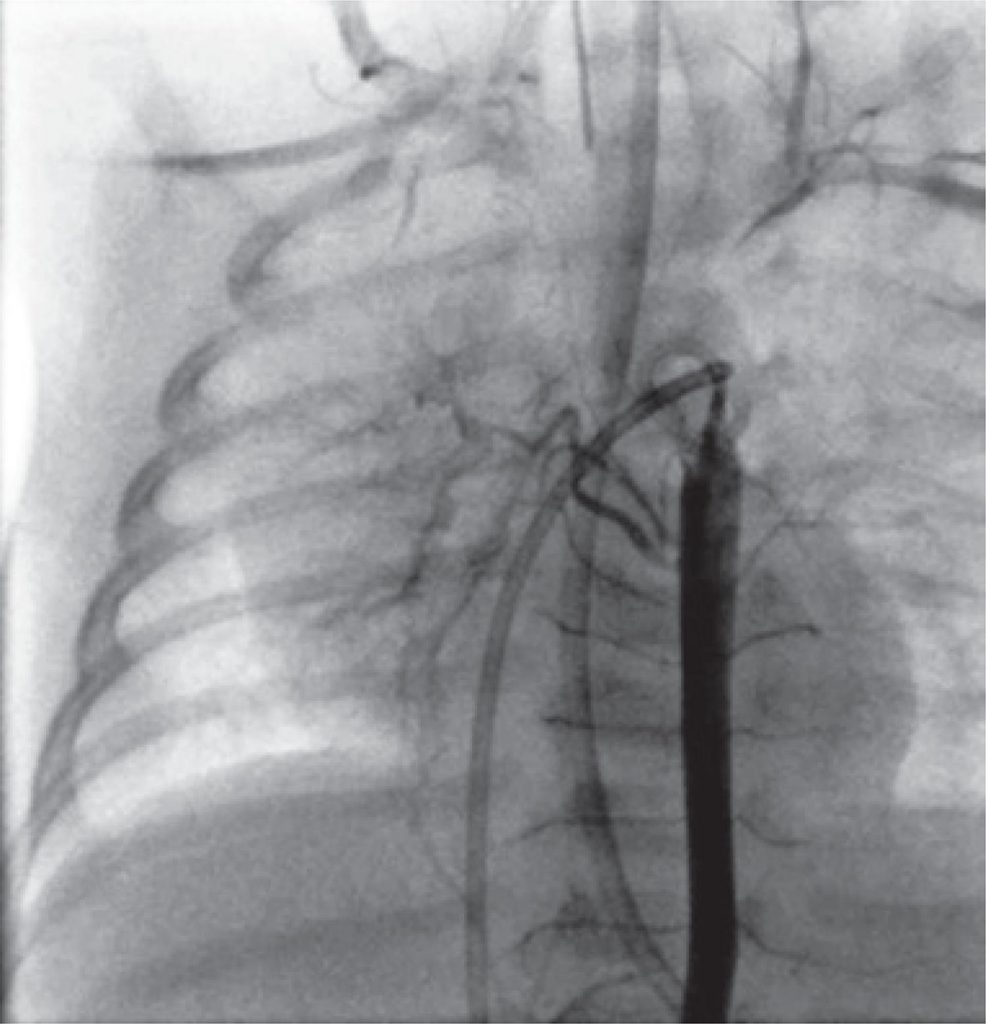

On transthoracic echocardiography, the heart appeared to be structurally and functionally normal. However the right pulmonary artery was not clearly evident. A computerized tomography angiography was performed to clarify this finding, but once again it was inconclusive. Nevertheless, hemitruncus and patent ductus arteriosus were ruled out. Subsequently he was catheterized and the pulmonary angiography showed agenesis of the right pulmonary artery (), ruling out occult pulmonary branch. The right lung was perfused by the bronchial arterial network () and no other anomalies were found.